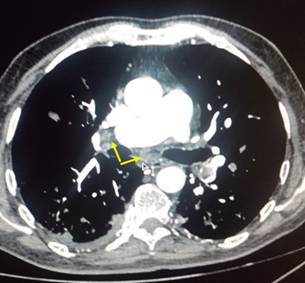

A su ingreso a urgencias, se encontró con TA 100/60 mmHg, FC 100 lpm; FR 35 r/min; oximetría de 80% al aire ambiental; cuello sin plétora yugular, campos pulmonares con estertores finos en ambas regiones infraescapulares; área precordial con ruidos cardiacos rítmicos, aumentados en frecuencia, con soplo regurgitante en mesocardio I/IV, sin irradiaciones ni galope; extremidades sin edema o signos de insuficiencia venosa superficial o profunda, pulsos y llenado capilar normales. El electrocardiograma mostró taquicardia sinusal y ondas T negativas de amplio voltaje en derivaciones precordiales V1 a V4 y en derivaciones inferiores (Figura 1). Con sospecha clínica de tromboembolia pulmonar (TEP), se solicitó dímero D, que reportó 5,000 u/L. Se estratificó al paciente en la escala de Wells modificada1 como de riesgo alto de TEP, por lo que se procedió a heparinización. El ecocardiograma transtorácico demostró dilatación importante de cavidades derechas, disfunción contráctil del ventrículo derecho y presión sistólica de la arteria pulmonar de 50 mmHg (Figura 2). Se efectuó angiotomografía pulmonar, que registró TEP submasiva con 45% de obstrucción de acuerdo al índice de Qanadli2 (Figura 3) y angiotomografía para valorar circulación venosa a nivel iliofemoral, donde se encontró trombosis venosa profunda izquierda (Figura 4). El grupo de respuesta para embolia pulmonar (PERT) decidió efectuar una trombólisis mediante sistema endovascular Eko-Sonic con acceso femoral derecho y administración de activador del plasminógeno humano recombinante/rt-PA, en infusión, utilizando una dosis de 10 mg en bolo inicial tanto en arteria pulmonar mediante el sistema mencionado como en vena iliaca mediante catéter multifenestrado intratrombo por vía percutánea con abordaje en vena poplítea ipsilateral; se prosiguió con aplicación de trombolítico a 0.5 mg/hora por 15 horas en la arteria pulmonar y vena iliaca izquierda, suspendiéndose en dicho momento por presencia de hemoptisis. La dosis total de alteplase fue de 35 mg. La evolución fue progresivamente hacia la mejoría; el ecocardiograma de control documentó disminución significativa de la presión arterial pulmonar y reducción en el tamaño de las cavidades derechas; la angiotomografía pulmonar de control demostró descenso en la carga de trombo en ambas ramas pulmonares y la vena iliaca.

Figura 3: Angiotomografía pulmonar en corte axial, donde se aprecia un trombo en la bifurcación de la arteria pulmonar, ocasionando trombosis submasiva de arteria pulmonar con 45% de obstrucción de acuerdo al índice de Qanadli.